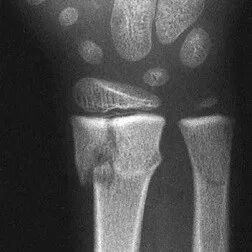

The second type, a buckle fracture, is also fairly common in children. It causes a small protrusion on the edge of the bone, as can be seen in the image below.